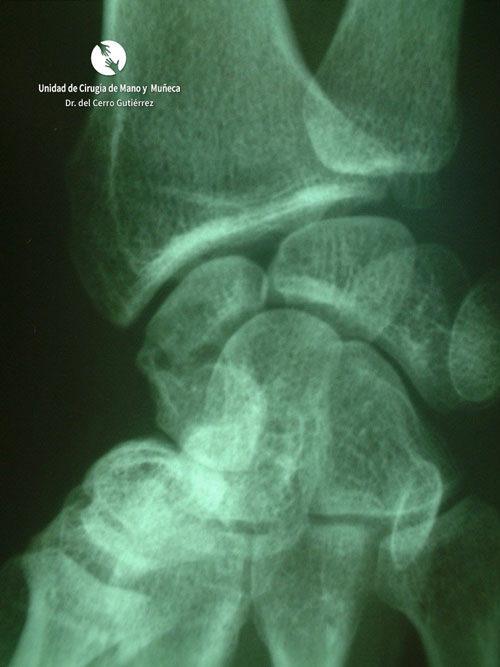

Fractura del polo proxima del escafoides de la mano

Fractura del escafoides. Polo Proximal

Fractura de escafoides de la mano. Polo Proximal

Fractura del escafoides. Pseudoartrosis del tercio medio